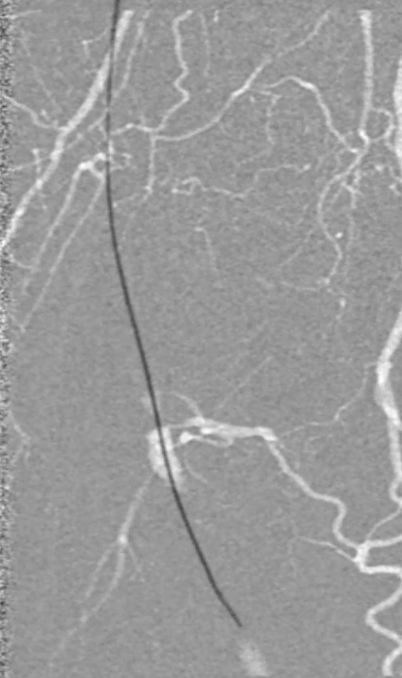

考虑到超声导管的使用以及导丝通过时顺滑度,认为病变大部分是真腔通过,因此考虑对股浅动脉减容处理。

预扩张:先用3mm球囊对病变段预扩张,便于后续器械导入。

保护伞置入:于腘动脉P2段水平放入6mm Spider 保护伞,预防栓塞。

定向旋切:采用新一代Hawk-Plus定向斑块旋切装置进行减容。对于支架内闭塞段,放大图像,确保刀头在可视范围内,反复旋切至接近支架边缘;

对于支架远端病变段,分别采用4个方向各旋切1次,完成初期减容。

器械优势:刀头弧度更大,与血管壁接触面积广,切除效率更高;